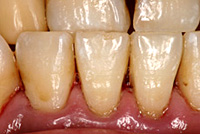

歯石除去前 |

歯石除去後 |

改善した歯は、歯ぐきが引き締まり歯の根の部分が露出し、歯が長くなり冷たい物が凍みることがあります。

歯石除去前

歯石除去後